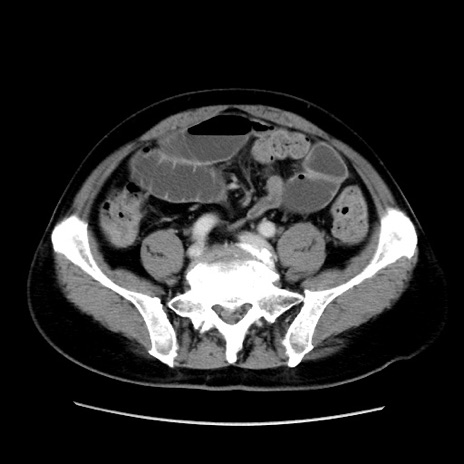

症例16(横断像)

冠状断像

【症例】 70歳代男性

【主訴】 腹痛、嘔吐

【現病歴】 約1ヶ月前より間欠的に腹痛と嘔吐あり、当院消化器内科を受診したところCTで多発する肝臓のLDAを指摘され、精査中であった。以降は消化器症状は安定していたが、2日前より嘔気と腹痛があり、同日より排便・排ガスが消失した。改善認めず、 本日、救急外来を受診した。

【既往歴】 大腸ポリープ切除後。

【身体所見】意識清明・会話良好、BT 36.3℃、BP 127/80mmHg、 P 80bpm、腹部:膨満あり、平坦・軟、上腹部正中および下腹部正中に圧痛あり、反跳痛なし、筋性防御なし。

【データ】WBC 7200、CRP 0.77